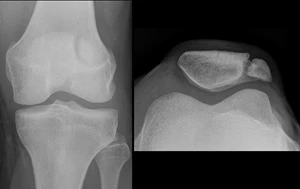

- Рентгенография коленного сустава двух проекциях

Известно множество классификаций переломов надколенника. Классификация переломов разнообразна и основана характере перелома и степени смещения его отломков. Переломы делятся на: без смещения (диастаз до 2—3 мм) и со смещением (диастаз более 3 мм или при неконгруэнтности суставной поверхности более 2 мм). Морфологически разделяют на поперечные, продольные, звёздчатые (оскольчатые) и отрывные переломы верхнего и нижнего полюсов. Также выделяют многофрагментные и остеохондральные переломы. Кроме того, выделяют открытые и закрытые переломы[3].

Перело́м надколе́нника (перелом коленной чашечки) — нарушение целостности надколенника из-за травмы, чаще встречающееся у мужчин и составляющее около 1 % от всех переломов. Причиной может быть прямой удар или резкое сокращение четырёхглавой мышцы бедра при быстром сгибании колена против её сокращения, что приводит к нарушению разгибательной функции сустава. Перелом сопровождается стойким болевым синдромом, ограничением движений и риском быстрого развития пателлофеморального артроза. Диагностика основана на клинических признаках, включая невозможность поднять прямую ногу, и подтверждается рентгенографией. Лечение зависит от характера повреждения: при отсутствии значительного смещения возможно консервативное лечение с помощью иммобилизации, при выраженном расхождении отломков требуется хирургическое восстановление с анатомической репозицией и жёсткой фиксацией, что позволяет быстрее вернуть подвижность и стабильность сустава[1][2].